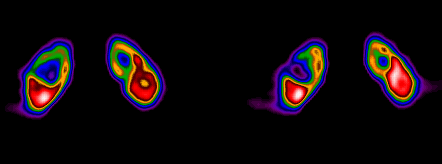

Hình 7. 99mTc -DMSA SPECT phát hiện u nang thận

Ưu điểm: DMSA tập trung đặc hiệu vào phần vỏ thận cho nên có độ nhạy cao trong chẩn đoán, đặc biệt là chẩn đoán nhiễm trùng đường dẫn niệu. Nó giúp cho ta nhận ra các tổn thương khu trú của thận và phân biệt được bệnh lành tính cũng như các tiểu thùy hay các cột Bertini bị bệnh do khối u, áp-xe, nhồi máu hay chảy  máu hoặc nang thận.